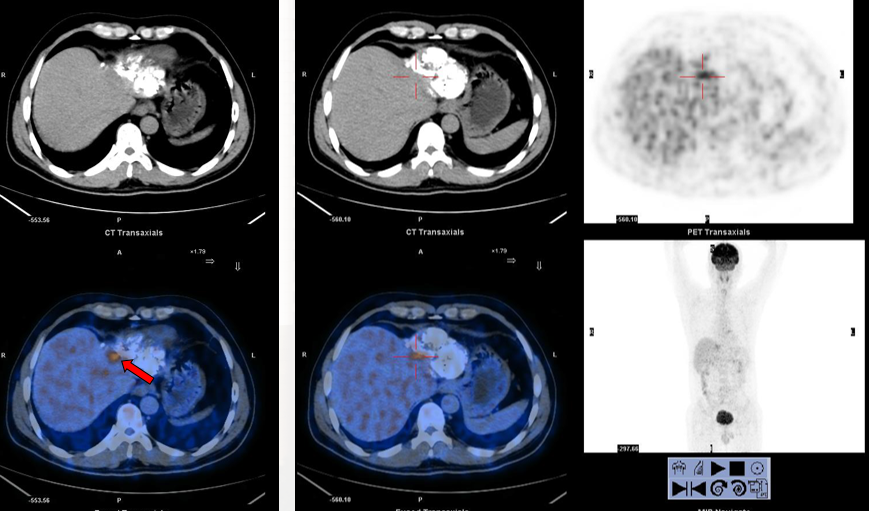

2011-08-22(第3次TACE后2个月) 行CT引导下微波消融+无水酒精固化术

2011-12-22(第一次消融后4个月) 入院复查:AFP:18.16 ng/ml。

PET/CT:见肝左叶病灶边缘代谢活跃区。

2011-12-26 对残留病灶行微波消融术:

2012-02-22(第二次消融后2个月)复查PET/CT:肝脏病灶代谢未见异常。AFP:3.52 ng/ml。

2012-06-29(第二次消融)后6个月 复查PET/CT:肝脏病灶代谢未见异常。AFP:2.74 ng/ml。

PET/CT在肝癌疗效评价中的作用:

无论是碘油沉积区还是非碘油沉积区都可能有残留病灶存在。

PET/CT对介入治疗后的残留病灶探测具有较高的灵敏度,可以用于介入治疗后的疗效评价。

其对判断肿瘤残留及指导消融治疗较增强CT检查具有更大的优势。